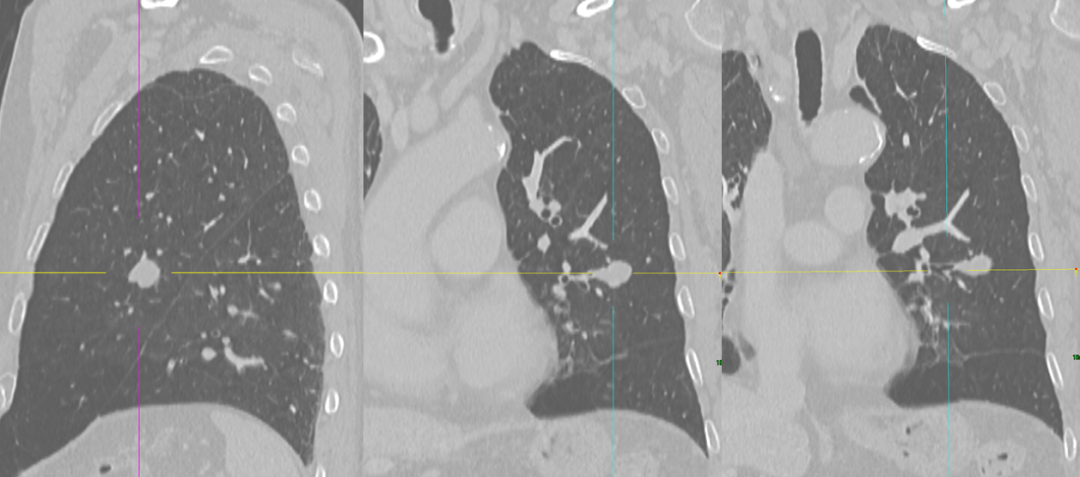

周围型肺小细胞肺癌1例|影像读片

• 影像学检查:3536585,2025-11-10 胸部CT增强

影像学表现